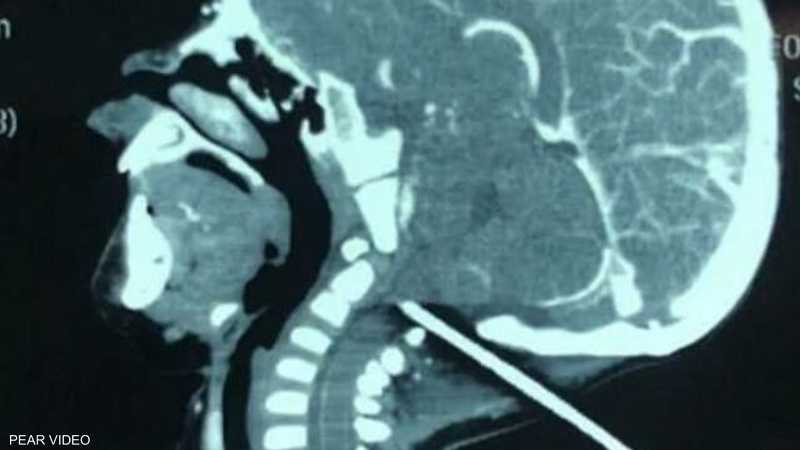

اخترق القصيب الحديدي جمجمة الرضيع

وبعد إخضاع رأس الرضيع للفحص بالأشعة السينية، تبين أن قسما كبيرا من القصيب مستقر في الجمجمة ولا يبعد سوى مليمترات عن الأوعية الدموية في قاع الدماغ.